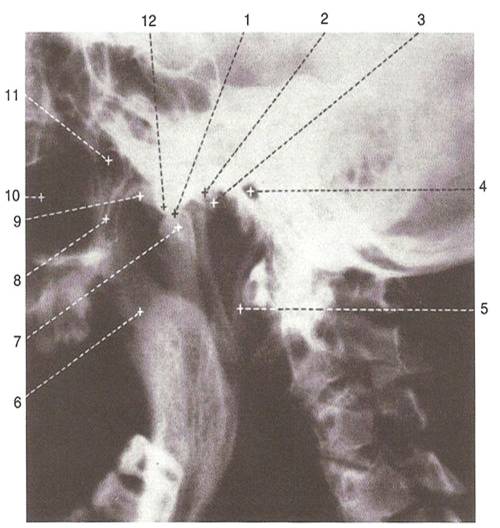

Рентген височной кости по Стенверсу: что важно знать